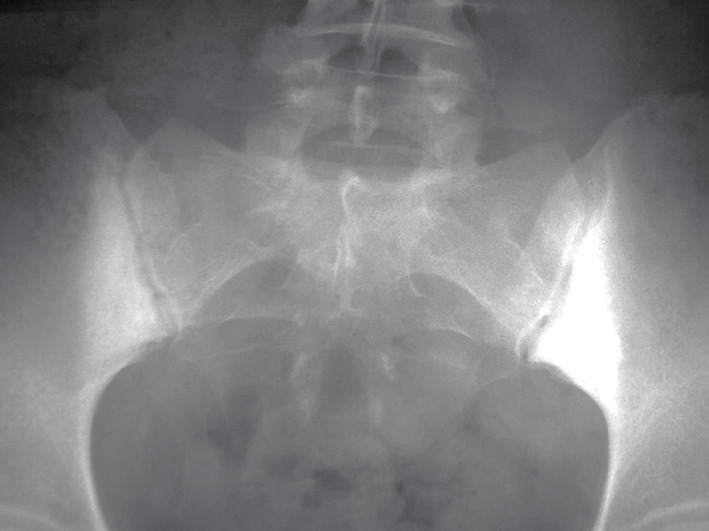

En radiographie standard, la sacro- iliite de la SpA se caractérise par une érosion associée à une condensation des berges sacro-iliaques pouvant évoluer vers l’ankylose. Cependant, cette condensation n’est pas spécifique à la SpA. On la retrouve dans l’ostéose iliaque condensante, affection de définition radiographique, le plus souvent asymptomatique, survenant classiquement chez la femme multipare. La condensation est alors localisée uniquement sur le versant iliaque, de forme triangulaire à base inférieure, sans atteinte de l’interligne (fig. 2 ).

En radiographie standard, la sacro- iliite de la SpA se caractérise par une érosion associée à une condensation des berges sacro-iliaques pouvant évoluer vers l’ankylose. Cependant, cette condensation n’est pas spécifique à la SpA. On la retrouve dans l’ostéose iliaque condensante, affection de définition radiographique, le plus souvent asymptomatique, survenant classiquement chez la femme multipare. La condensation est alors localisée uniquement sur le versant iliaque, de forme triangulaire à base inférieure, sans atteinte de l’interligne (